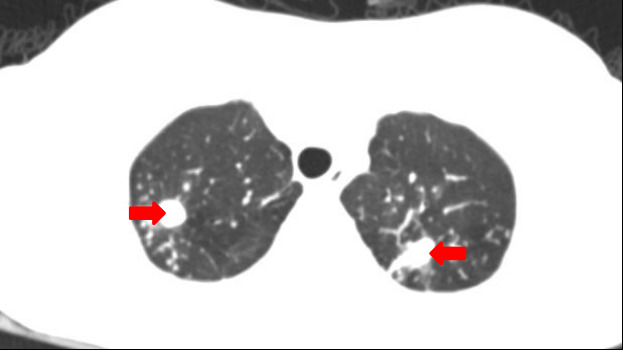

周海依介绍,结核病是由结核分枝杆菌引起的传染病,除了引起肺结核之外,还可侵犯身体其他多个部位。皮肤结核是结核分枝杆菌直接侵犯皮肤或由其他器官结核病灶内的结核杆菌经血行或淋巴系统播散到皮肤组织所致的皮肤损害,发病率低,常表现为皮肤增厚、结节、溃疡、脓肿4型,多就诊于皮肤科,很容易被误诊为结节性红斑、真菌感染、狼疮等自身免疫性疾病,从而使用激素及免疫抑制剂,导致结核播散、皮损反复迁延不愈,甚至永久性毁容。

2、结核病是传染性疾病,应提高对疾病的认识和防范,若出现持续2周以上的发热、胸痛症状,应及时进行胸部CT检查或到专科医院进行结核筛查,如不慎患上结核,应配合医生规范治疗。